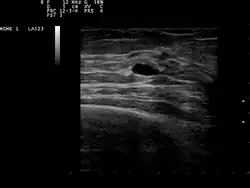

Ultrasound scan showing a small cyst in the breast | |

The cystic nature of a breast lump can be confirmed by ultrasound examination, aspiration[6] (removal of contents with needle), or mammogram. Ultrasound can also show if the cyst contains solid nodules, a sign that the lesion may be pre-cancerous or cancerous. Examination by a cytopathologist of the fluid aspirated from the cyst may also help with this diagnosis. In particular, it should be sent to a laboratory for testing if it is blood-stained.

Patients suspected of breast cysts will normally be given a diagnosing mammogram, although they are not suspected of cancer. This type of mammogram provides the doctor with the possibility of performing a breast ultrasound at the same time and this is the reason why they are often preferred over the screening mammograms. Breast ultrasound is considered the best option when diagnosing breast cysts because it is 95 to 100% accurate, it provides a clear image on the cyst's appearance (simple or complex) and it may also distinguish between solid lumps and fluid-filled cysts, which a mammogram cannot do.[7] Breast ultrasounds are performed with the help of a handheld medical instrument which is placed on the skin, after a special type of fluid has been applied on it. The instruments picks up the echo resulted from the sound waves it sends to the breast. These echoes are transmitted to a computer which translates it into a picture.